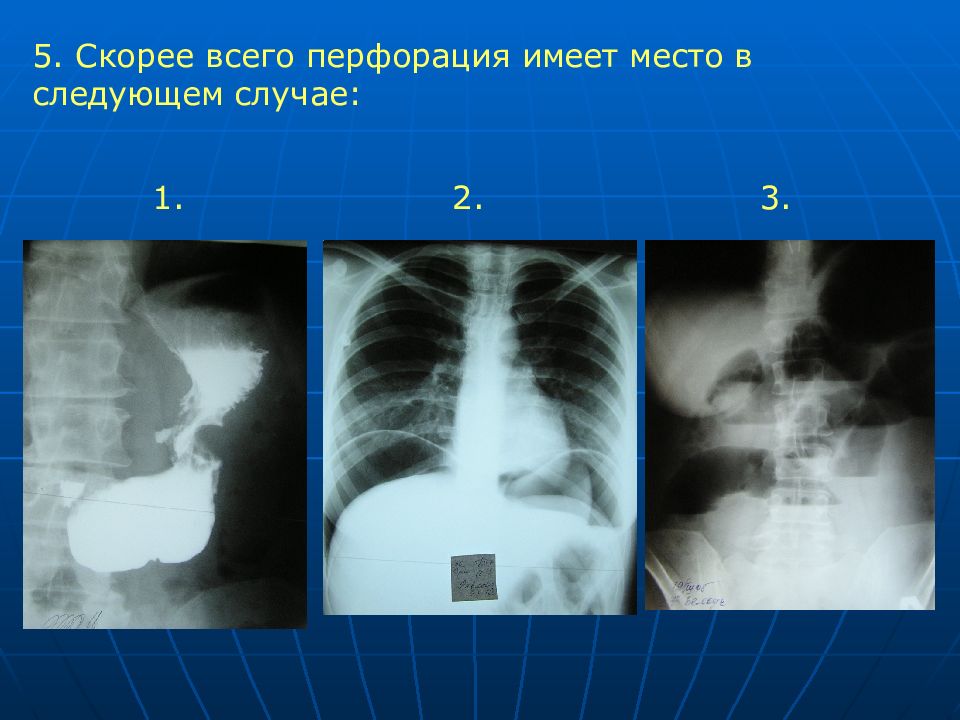

Современные технологии в медицине: рентгенодиагностика заболеваний желудка